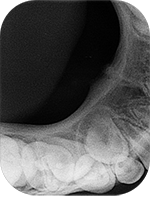

図❷ 初診時のデンタルX線写真

画像所見:歯軸方向での口底部デンタルX線画像では、とくに特異的な所見は認められなかった(図❷)。